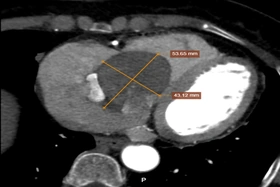

Người bệnh nữ (68 tuổi) ở Việt Trì, bị zona thần kinh vùng thành ngực và đau nhiều ở khu vực bị zona. Người bệnh đi khám thì phát hiện có khối bất thường kích thước lớn ở tim bên phải.